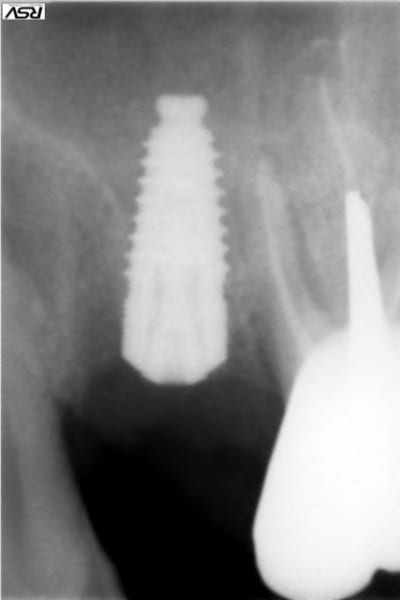

Présentation du cas : extraction de 26 , attente 2 mois cicatrisation, hauteur résiduelle estimé à 5 mm , mauvaise surprise après avoir oté le provisoire, très belle crète bien large mais invaginée en son centre.

Forage au milieu à 3mm + effraction du plancher ,manoeuvre de Walsava OK, bourrage au Gen Oss (0.5cc) , re Walsava, et implant IDCAM 10/5.2 bloqué au maximum .

sur la radio post-op, l'espace entre l'implant et la pré-molaire, non comblé, ne causera pas de problème ?

J'aurais tenter un SA-3, pour comblé plus large et évité ce vide, qui est un ramasse bactérie dans le sinus...

peut être , mais je parie plutot sur une remontée générale du plancher dans ce secteur, vu la faible distance avec la prémolaire.

On va faire comme d'hab, on va attendre les photos à 6 mois pour savoir qui a raison.

Tiens jette un coup d'oeil sur la partie mésial de cet implant sans comblement où 3 spires ont été englouties dans la cicatrisation osseuse